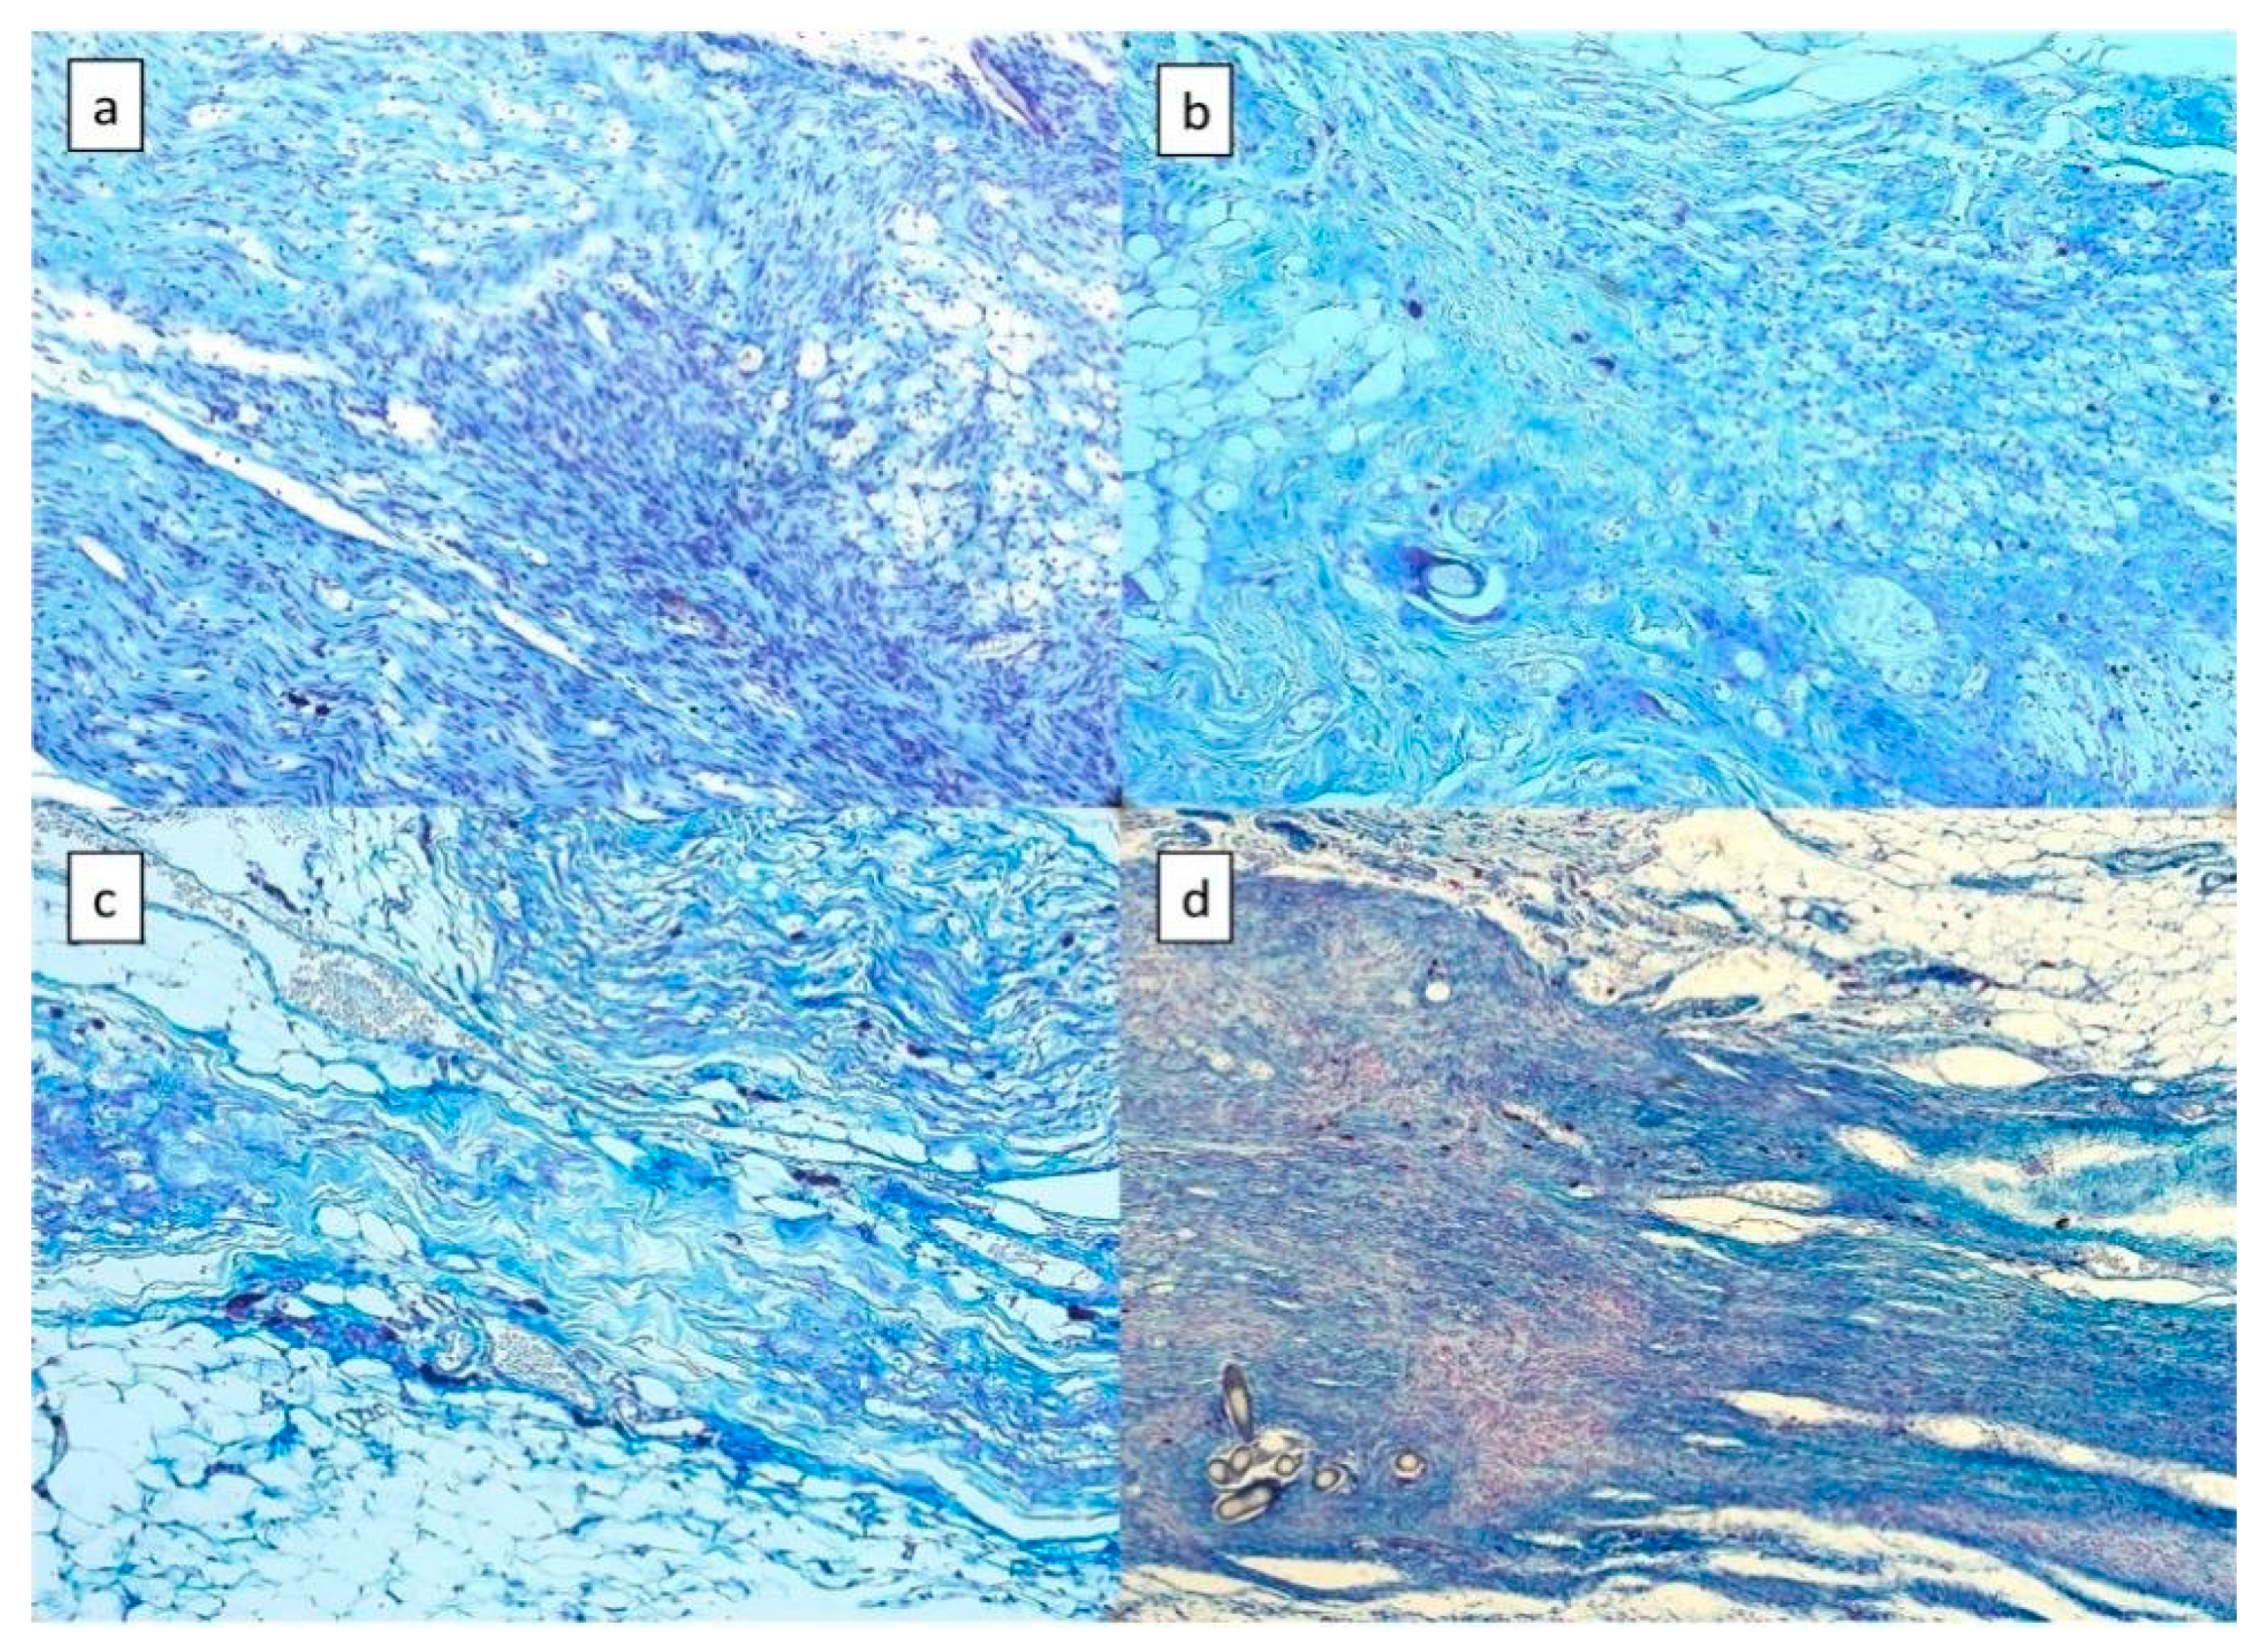

3.1. Mast Cells

3.1.1. Assessed by Luxol Fast Blue